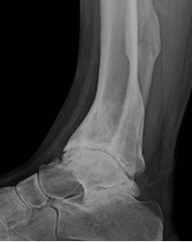

Fig 42. Artropatía neuropática. Patrón atrófico.

A: Rx AP y B: TAC reconstrucción coronal. Fractura del maléolo interno, con osteopenia del tobillo y lesiones osteocondrales de la tibia y el talo.